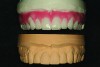

Fig 20. The completed ceramic restorations on the maxillary master model are shown.

Figure 20

Fig 21.  The completed ceramic restorations on the mandibular master model are shown.

Figure 21